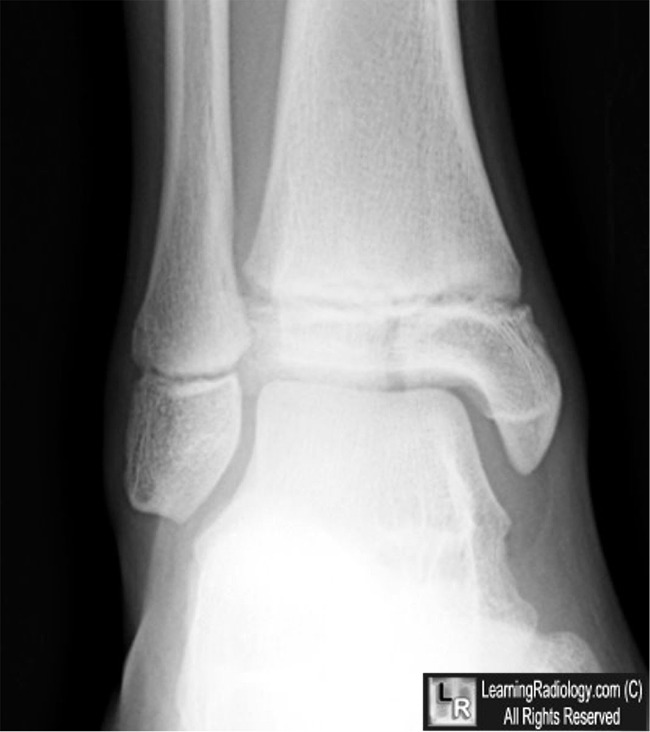

Salter III

- Salter-Harris III Fractures

- Involves the epiphyseal plate and the epiphysis itself

- Since the epiphysis is involved, damage to the articular cartilage can occur

- Growth disturbance is uncommon

- A Tillaux fracture of the ankle is a Salter-Harris III fracture

Salter-Harris III Epiphyseal Fracture. There is a longitudinal lucency (blue arrow) in the epiphysis that represents a fracture. All Salter-Harris fractures, by definition, involve the epiphyseal plat, even though those fractures may not be visible.